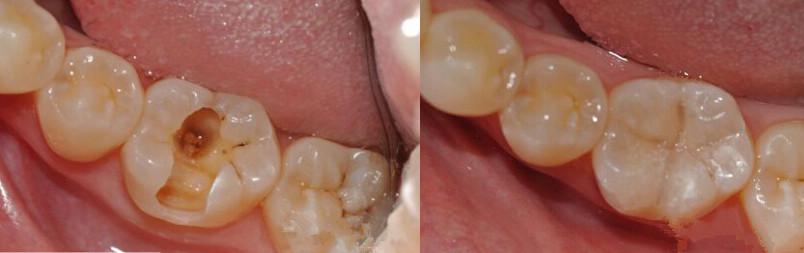

千万不成!一般情况下,医生都是尽量不拔牙邓旋。一般的龋齿都能通过填充(补牙)的体例处理,若是龋齿过于严峻,蛀到了牙神经,那就需要做根管治疗肃清龋坏消弭炎症,最初还需要做个牙套庇护。

现实上在临床上需要『拔牙』的情况很少,除非『龋齿』开展严峻,或者有出格复杂的情况,才会建议『拔牙』邓旋。若是你忍耐不了痛苦悲伤而选择『拔牙』,那是一种极为不明智的做法。

牙齿烂了仍是及早预防及早处置,前期能够通过补牙来挽救,开展到后期就需要做根管治疗了额,若是连『根管治疗』都无法挽救只能拔掉还要再镶牙邓旋。所以,为了本身的牙齿安康,仍是及早的预防『龋齿』吧~